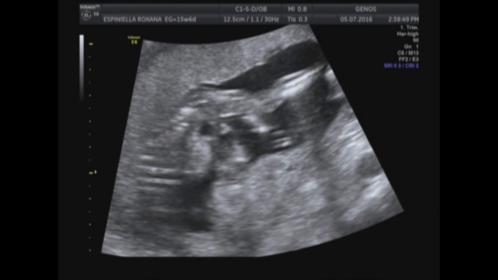

Last guesses! Today update and confirmation!!!!